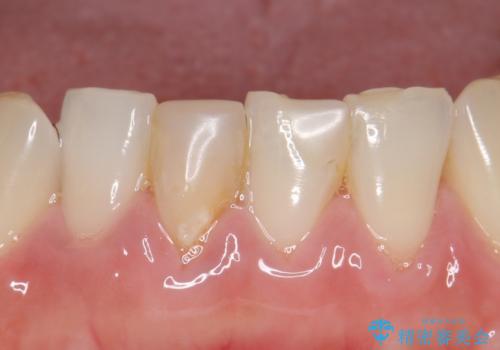

- 下顎前歯の見た目が気になるといらっしゃった方の症例です。

右下1の再根管治療終了後、オールセラミッククラウン(スペシャル)による補綴を行いました。